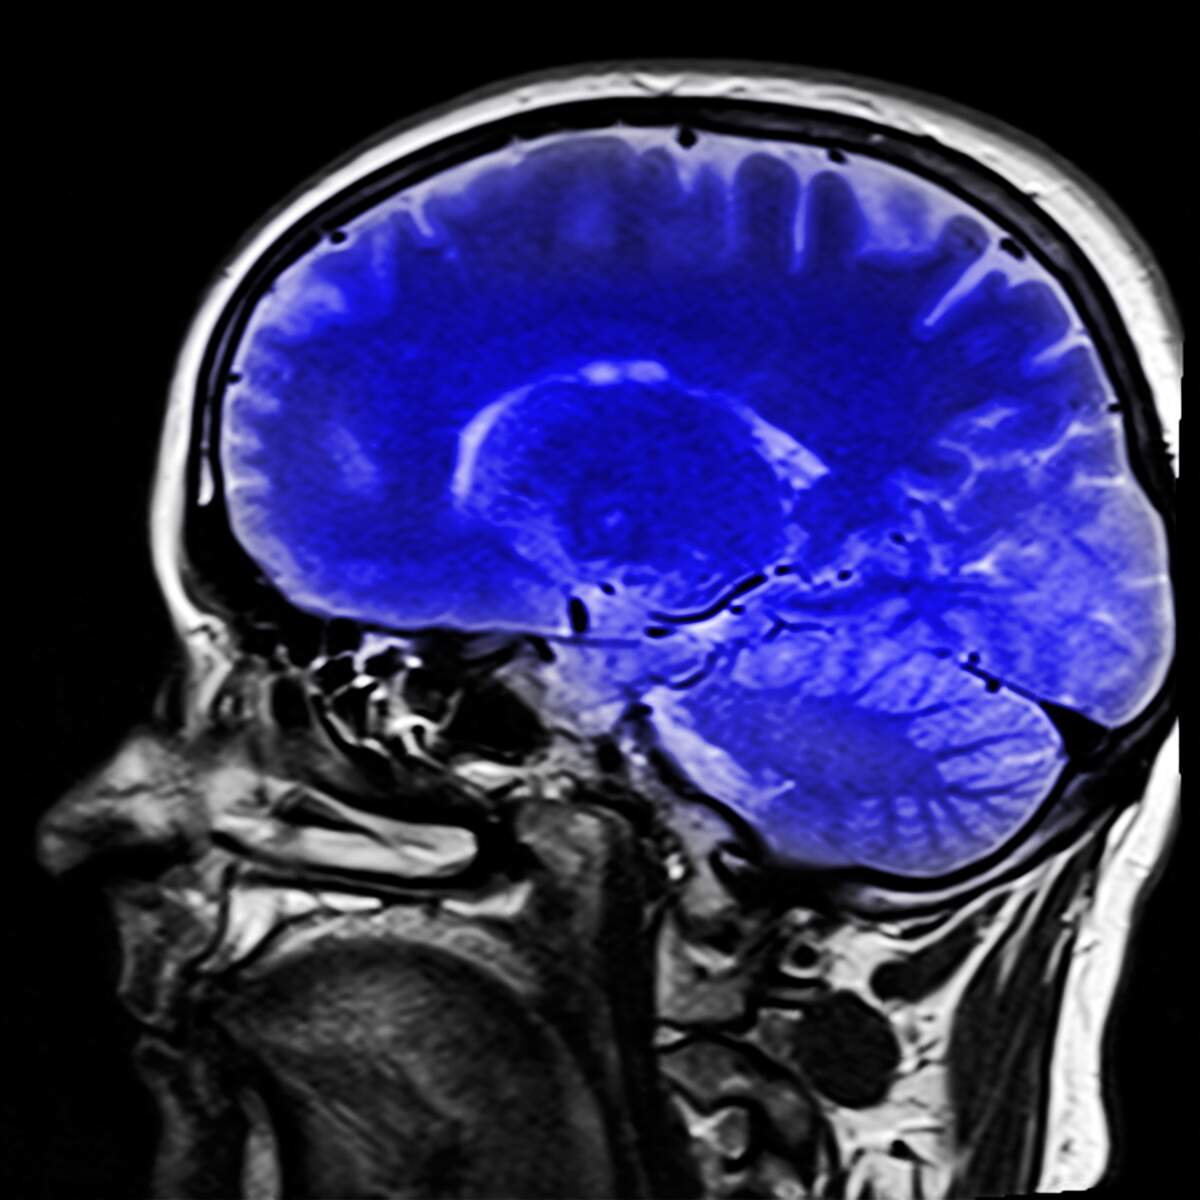

Thank you to @DrPeteTaylor for highlighting how iodine deficiency is a UK public health issue and proposing steps to address this. Please share to get this message heard. #iodine #pregnancy #CognitiveDevelopment

My piece in bylines. Iodine, UK policy and brain growth: a question of intelligence. Grateful if people could amplify this @Soc_Endo @TheEndoSociety @britishthyroid @ThyroidBritish @thyroiduk_org centralbylines.co.uk/news/health/io…

Thank you to @DrPeteTaylor for highlighting how iodine deficiency is a UK public health issue and proposing steps to address this. Please share to get this message heard. #iodine #pregnancy #CognitiveDevelopment

My piece in bylines. Iodine, UK policy and brain growth: a question of intelligence. Grateful if people could amplify this @Soc_Endo @TheEndoSociety @britishthyroid @ThyroidBritish @thyroiduk_org centralbylines.co.uk/news/health/io…